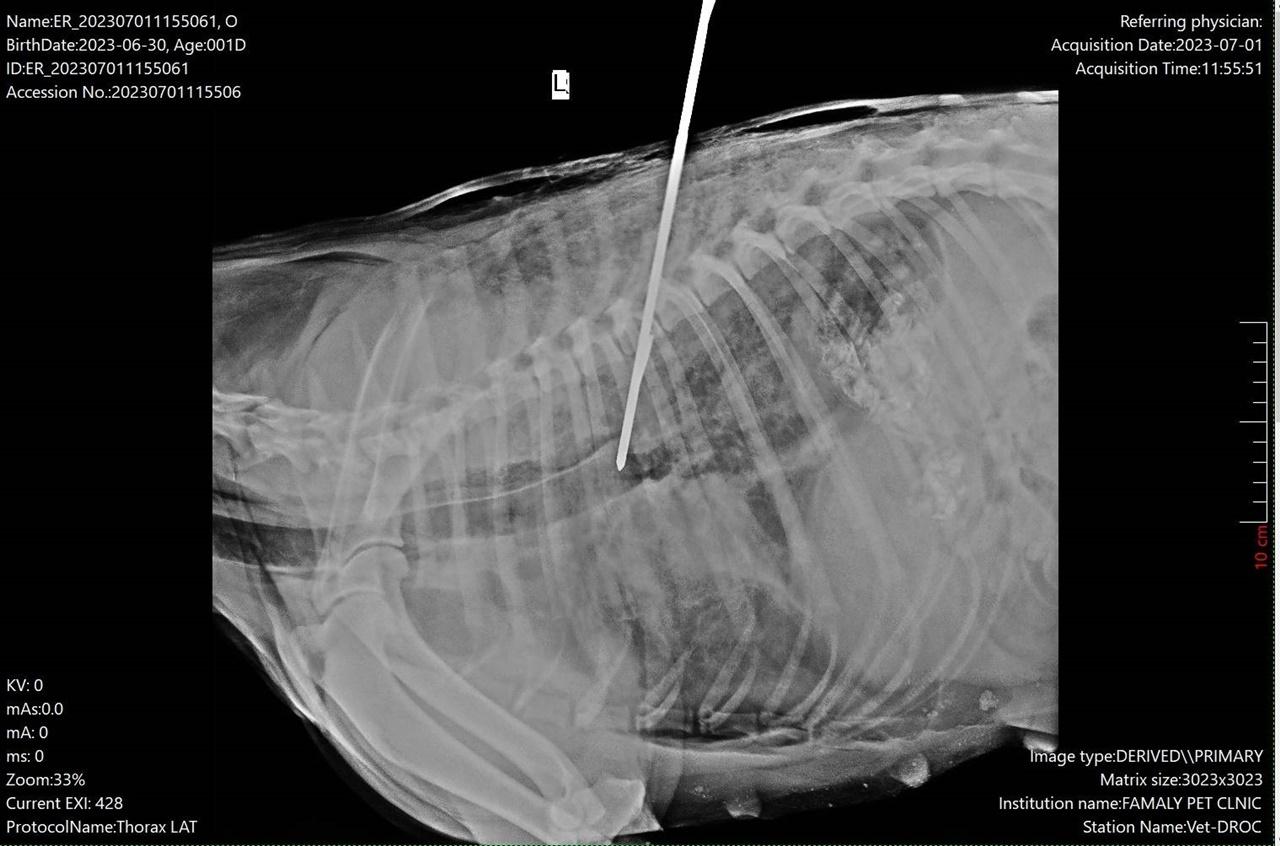

เมื่อเวลา 15.00 น. วันที่ 23 ก.ค. 2566 ผู้สื่อข่าวลงพื้นที่ไปยังบ้านเลขที่ 9 หมู่ที่ 7 ต.คลองสวน อ.บางบ่อ จ.สมุทรปราการ พบกับ นายเสนีย์ ชุ่มศิริ อายุ 44 ปี อาสาสมัครมูลนิธิป่อเต็กตึ๊งบางบ่อ ผู้ใจบุญรับเลี้ยงเจ้าดำสุนัขแม่ลูกอ่อนกับลูกอีก 3 ตัว ที่เพิ่งลืมตามาดูโลกได้เพียง 2 วัน หลังรอดชีวิตอย่างหวุดหวิด จากการถูกคนใจบาปยิงด้วยลูกดอกเหล็กยาวประมาณ 20 เซนติเมตร ฝังลึกเข้าไปในลำตัวด้านขวา เกือบทะลุถึงปอด มีอาการหายใจติดขัด ชีพจรอ่อน แต่ได้รับความช่วยเหลือทันเวลา

นายเสนีย์ เล่าว่า ตอนเกิดเหตุ ตนเป็นคนไปรับเจ้าดำนำส่งให้หมอรักษาอาการบาดเจ็บ หลังจากอาการดีขึ้นแล้ว หมออนุญาตให้กลับไปรักษาต่อที่บ้านได้ แต่ไม่มีใครแสดงตัวเป็นเจ้าของสุนัข ตนเห็นแล้วสงสารจึงอาสานำมาเลี้ยงเอง โดยดูแลอย่างดีเป็นเวลาเกือบเดือน และเมื่อ 2 วันที่ผ่านมา ภรรยาโทรบอกว่าเจ้าดำคลอดลูกออกมา 3 ตัว เป็นเพศเมีย 2 ตัว, เพศผู้ 1 ตัว ตนรู้สึกแปลกใจเนื่องจากตอนที่บาดเจ็บนำส่งให้หมอรักษาไม่พบว่ามีอาการท้อง อาจเป็นเพราะเจ้าดำถูกลูกดอกเหล็กแทงทะลุลำตัวด้านขวา หมอจึงไม่ได้พลิกตัวเอกซเรย์อย่างละเอียด ทุกคนคิดว่าเป็นสุนัขอ้วนเฉยๆ แต่หลังจากเจ้าดำคลอดลูกออกมา ตนก็ดีใจและพร้อมจะดูแลตลอดไป

ด้าน นายอภินพ เหลืองรุ่งทรัพย์ หัวหน้าทีมอาสาสมัครมูลนิธิป่อเต็กตึ๊ง บางบ่อ ได้ย้อนเล่าเหตุการณ์ให้ผู้สื่อข่าวฟังว่า รับแจ้งเหตุพบสุนัขเพศเมีย สีดำ ถูกลูกดอกเหล็ก สำหรับใช้ยิงปลา ยิงฝังลึกเข้าไปบริเวณลำตัวด้านขวา นอนแน่นิ่ง หายใจรวยริน มีแนวโน้มอาจเสียชีวิต เหตุเกิดบริเวณบ่อน้ำในสนามกอล์ฟสุภาพฤกษ์ ถ.มหาวิทยาลัยอัสสัมชัญ ต.บางบ่อ อ.บางบ่อ จ.สมุทรปราการ หลังรับแจ้งจึงเดินทางเข้าตรวจสอบ และพบสุนัขดังกล่าวตามที่แจ้ง ทีมกู้ชีพฯ จึงเร่งให้การช่วยเหลือ นำส่งไปรักษาด่วนที่ รพ.สัตว์บ้านหมอป๊อป ทำการผ่าตัดเอาลูกดอกเหล็กออกมา โชคดีที่ทีมกู้ชีพฯ เข้าช่วยและนำส่งถึงหมอเร็ว เจ้าดำจึงรอดชีวิตอย่างหวุดหวิด แต่ต้องนอนเฝ้าดูอาการอีกประมาณ 3 วัน หากไม่มีอาการอื่นใดแทรกซ้อน ก็สามารถกลับบ้านได้